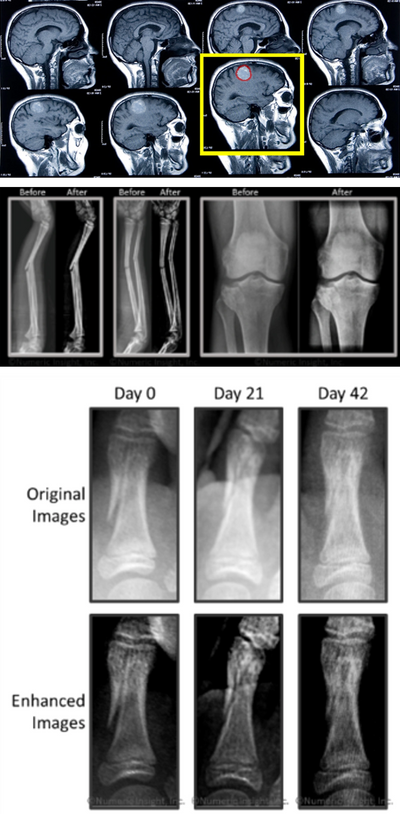

Medical imaging is a crucial aspect of clinical care today. In every hospital or imaging center, a huge amount of data is generated on a daily basis from various modern imaging technologies. Further, the frequent use of multimodality imaging adds to the amount of data being acquired.

One of Numeric Insight’s noted strengths – Machine Learning – plays a vital role in the medical imaging field. Biological objects such as lesions do not come in standard shapes, nor can they be represented by equations. This inherent variability calls for a system that can “learn from examples” in order to perform common tasks necessary for diagnosis. Also, since medical images rarely yield clinical value when taken in isolation, integration with other biomedical signals and non-image information resources is needed.

New machine-learning algorithms are always being sought in the medical imaging field either to better solve diagnostically challenging problems or because new modalities and methodologies are constantly being introduced. As an example, consider molecular imaging which allows doctors to distinguish between normal and pathological biological processes by seeing the interactions of signaling molecules with sites on cell membranes and extracellular matrix.

Numeric Insight makes available to the medical imaging community its extensive experience in statistical pattern recognition, image segmentation and image registration to prototype new algorithms quickly and efficiently; and deploy tools as standalone or web-based applications.